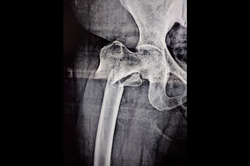

Neck Femur Fracture